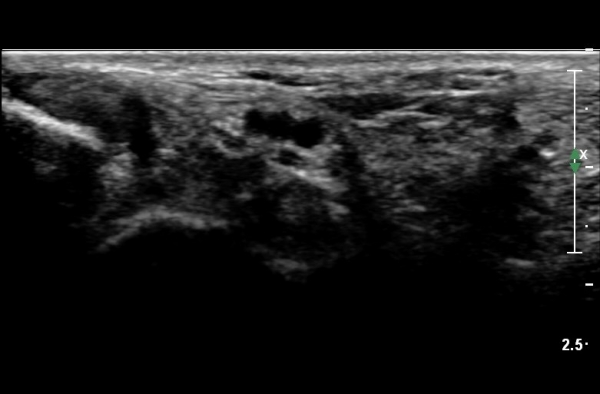

¹ß¸ñÅͳΠȾ´Ü¸é°Ë»ç¿¡¼­ ³»Ãø º¹»ç»À ³»Ãø¿¡ Èİæ°ñ°Ç, ¹ß°¡¶ô±¼°î°Ç°ú ¾öÁö¹ß°¡¶ô±¼°î°Ç

»çÀÌ¿¡¼­ Èİæ°ñ½Å°æÀÌ °üÂûµÇ°í ½Å°æÀÇ Ç¥Ãæ¿¡ µ¿¸Æ°ú Á¤¸ÆµéÀÌ °üÂûµÈ´Ù(»çÁø 1).